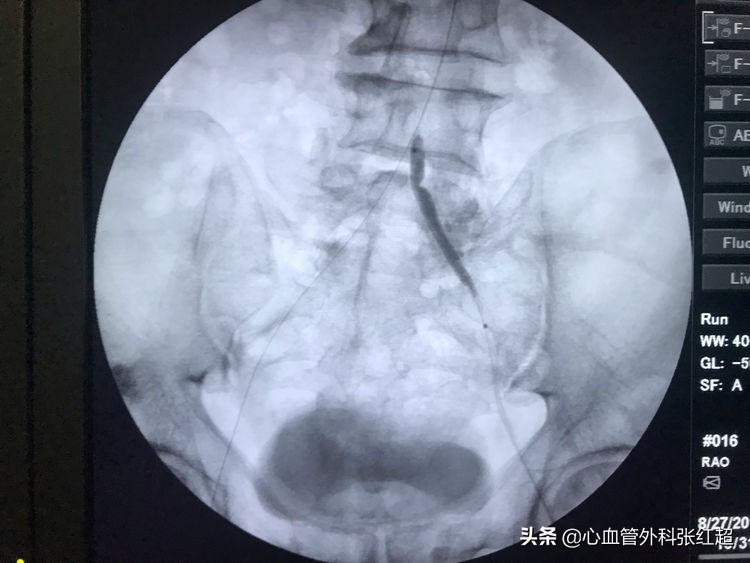

血管造影剂排空快,对侧显影淡,说明血管内血流速度快。

屈曲部稍有残余狭窄。不用硬扩,支架可以在术后贯性序扩。

放两枚支架更容易保证远端释放到位

术后足背、胫后动脉搏动均恢复。